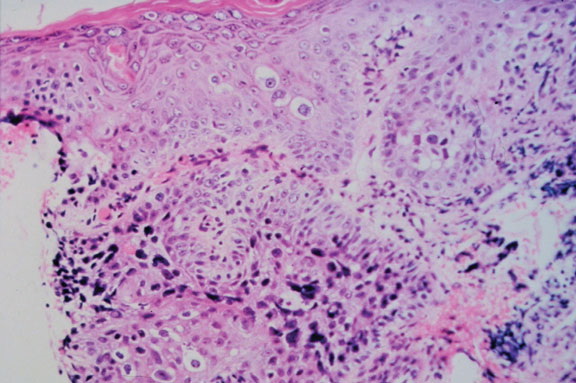

Sebaceous carcinoma = الكارسينوما الدهنية